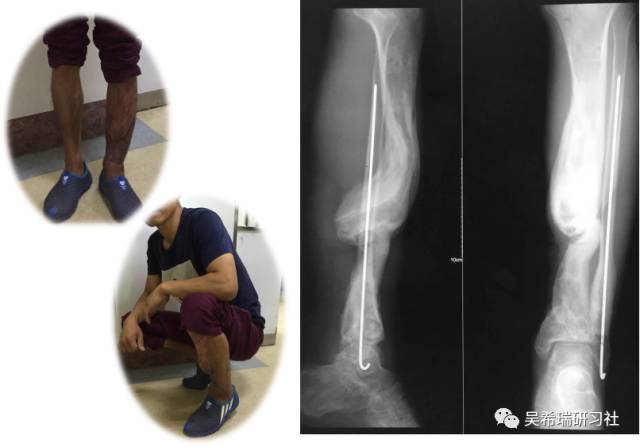

病例8

双下肢车祸外伤保肢的理由是足底皮肤好

TIPS:清创&盐水冲洗(不用双氧水)VSD骨水泥技术&开放植骨单边外固定架(下胫腓联合固定)早期下地 生理应力 + 机械应力游离植皮 / 不用皮瓣清创时游离皮质骨去除胫跖骨牵引技术防治&纠正足下垂